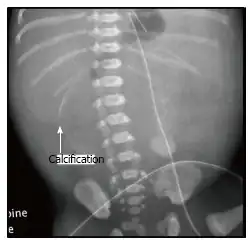

X-ray of a newborn with meconium pseudocyst resulting from bowel perforation. In this case the cause was atresia of the terminal ileum. There is a fine rim of calcification surrounding the big pseudocyst which shifts the other intestinal structures outwards. | |

Meconium peritonitis refers to rupture of the bowel prior to birth, resulting in fetal stool (meconium) escaping into the surrounding space (peritoneum) leading to inflammation (peritonitis). Despite the bowel rupture, many infants born after meconium peritonitis in utero have normal bowels and have no further issues.

Meconium peritonitis is sometimes diagnosed on prenatal ultrasound[3] where it appears as calcifications[4] within the peritoneum.